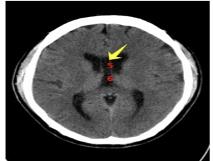

第五、六脑室

国内将透明隔腔亦称第五脑室;Vergae腔或称穹隆腔,亦称第六脑室;透明隔腔不属于脑室系统,因为它不具备脑室的组织结构特征,内壁并未衬有室管膜细胞,内含有的液体也与通常的脑室系统不同,腔内的脑脊液通过透明隔膜过滤和隔膜静脉及毛细血管重吸收。

我们临床医生阅片要注意:透明隔腔多为生理性的,多无临床症状,而透明隔囊肿多为病理性的,过一段时间可能出现临床症状,甚至要手术治疗。